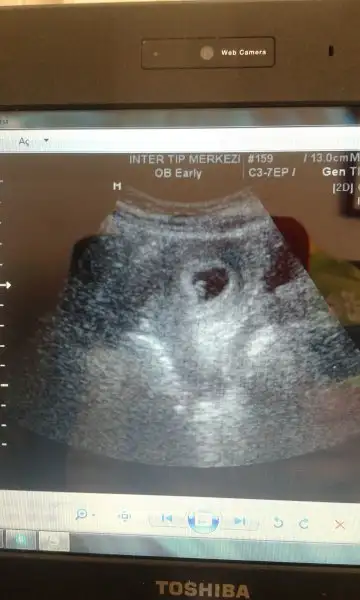

Benimde kizimda senin kiz gibiydi oglumdada simdiki ultrasyon resmin gibiydi. Sanirim bebosin oglan canim :)Eki Görüntüle 1895776 bu kızım 7 yıl önceki ultrason görüntüsü. Eki Görüntüle 1895777 buda şimdi ki

Senin oglum keseye göre tutmus buda kiz bence cünkü teori sende tutuyo :)Karından usg.ilk foto 6+3 ikinci foto 7 haftalık.

6 ile 8 hafta arası usg görüntü varsa gönder.arkadaşlar yorum yaparlar.hayırlısı olsun